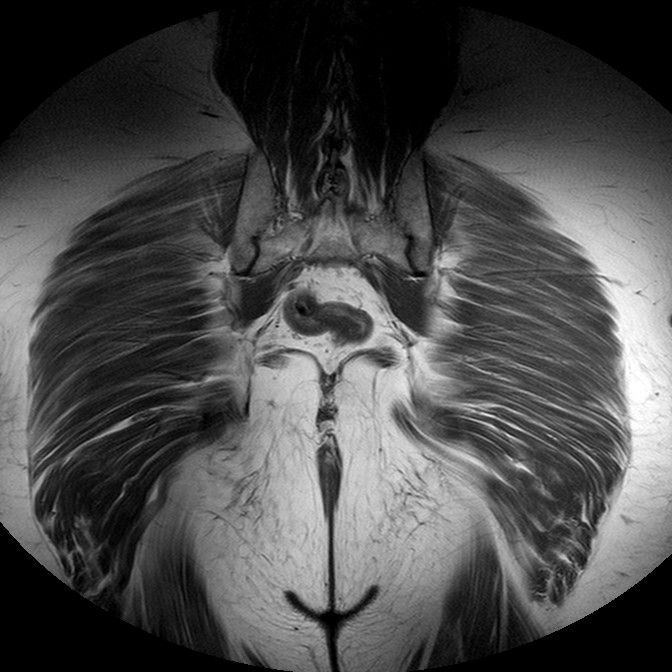

Esami: RMN BACINO

T1w TSE

Evidenti e simmetriche alterazioni osteofitosiche in regione coxo femorale con riduzione delle rime articolari. Degenerazione completa del cercine glenoideo. Non attuali segni di versamento articolare. Non segni di edema osseo che escludono attuale algodistrofia od osteonecrosi. Lieve e simmetrica riduzione del trofismo della muscolatura glutea.